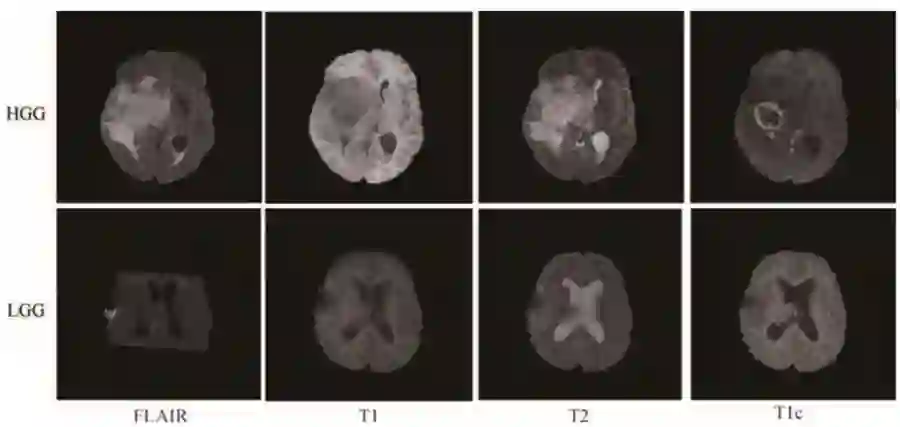

MRI脑肿瘤图像分割的深度学习方法综述

作者:江宗康,吕晓钢,张建新,张强,魏小鹏

第一作者单位:

大连大学先进设计与智能计算省部共建教育部重点实验室

关键词:磁共振成像;脑肿瘤;人工神经网络;深度学习;分割